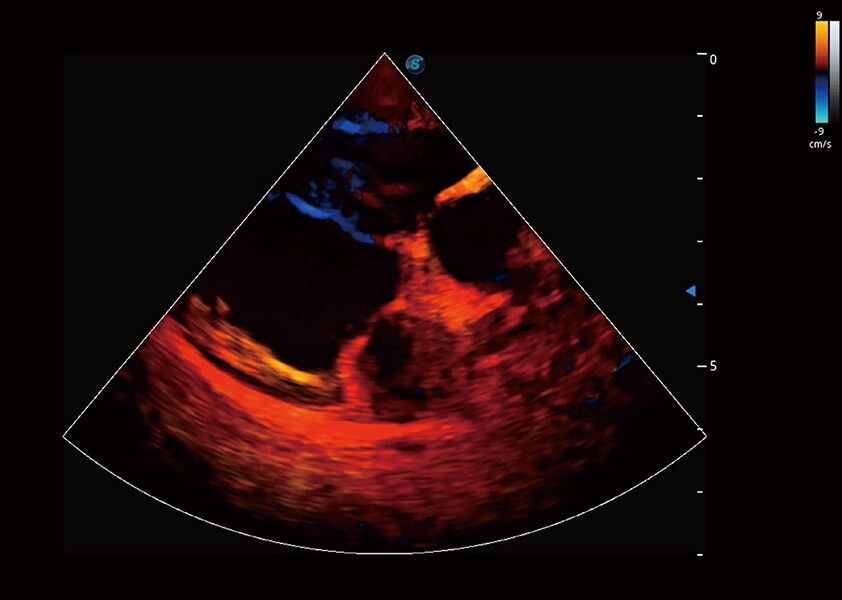

ProPet 60 作为一款高端台式动物超声设备,为动物医生的日常诊断提供了一系列贴合动物临床需求、解决临床实际问题的高级成像功能。凭借全系列高清探头,满足医生对腹部、心脏、生殖、浅表、肌骨等成像的所有需求,切实帮助您提升检查效率,提高诊断信心。

动物是人类最亲密的朋友和最值得信赖的伙伴。云顶集团官网也一直致力于探索动物专用的超声影像解决方案。 全新推出的ProPet系列,是云顶集团官网在动物超声影像智能化、专业化、精准化的一次跨越式革新。动物不能用言语来表述自己的不适,通过超声影像,ProPet系列搭建了动物医生与不同物种沟通的“桥梁”,为动物医生注入了“治愈之力”。